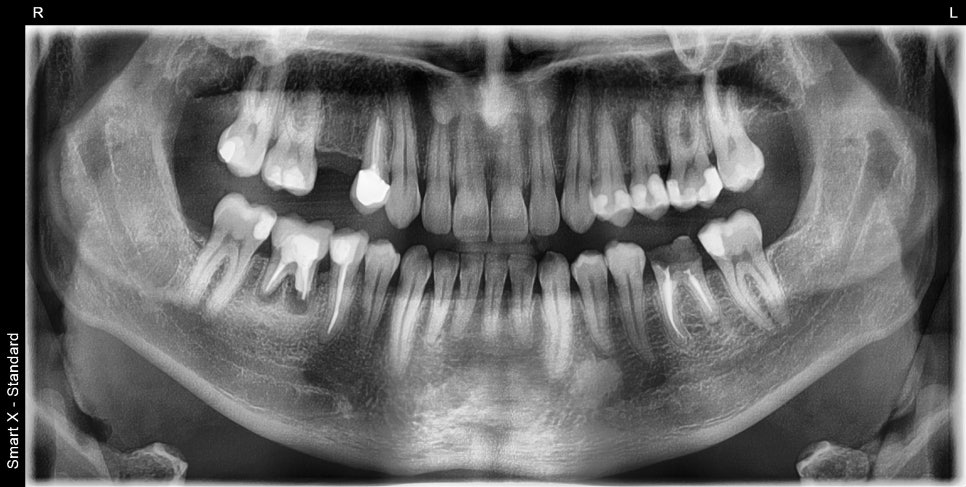

This is the initial panoramic X-ray of the patient who visited with pain after treatment overseas a long time ago.

The first large molar on the lower right had severe root apex inflammation, and the first large molar on the lower left had severe decay with crown fracture observed.